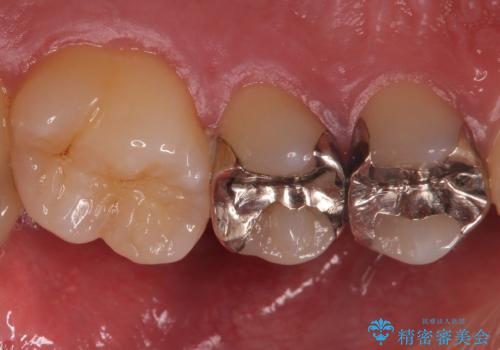

- 外から見える範囲の銀歯のやり替えをご希望で来院されました。

セラミックインレーでの治療となります。

- 左上45 セラミックインレー 77,000円×2本 費用は治療当時の料金となります